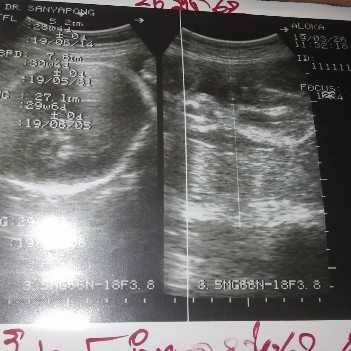

ตั้งครรภ์

นี่ผู้ชายรึป่าวค่ะ???

มาสารภาพว่าคุณหมอชี้ให้เราดูทุกรอบว่านี่จู๋ลูก แต่เราไม่เคยดูออกเลยค่ะ ลองถามคุณหมอดูนะคะ หรือบางทีคุณหมออาจจะรอให้ชัดก่อนแล้วค่อยแจ้งเพศน้องอีกทีนะคะ